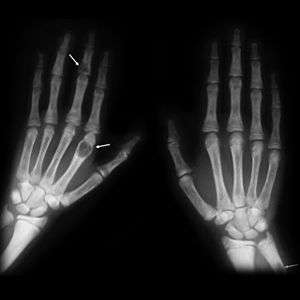

X-rays may also be used to diagnose the disease. Usually, these X-rays will show extremely thin bones, which are often bowed or fractured. However, such symptoms are also associated with other bone diseases, such as osteopenia or osteoporosis.[27] Generally, the first bones to show symptoms via X-ray are the fingers.[20] Furthermore, brown tumors, especially when manifested on facial bones, can be misdiagnosed as cancerous.[27] Radiographs distinctly show bone resorption and X-rays of the skull may depict an image often described as "ground glass" or "salt and pepper".[28][29] Dental X-rays may also be abnormal.[3]

Generally, the first bones to be affected are the fingers, facial bones, ribs, and pelvis.[20][21] Long bones, which are longer than they are wide, are also among the first affected.[21] As the disease progresses, any bone may be affected.[16]

The brown tumors commonly associated with OFC display many of the same characteristics of osteoclasts.[21] These cells are characteristically benign, feature a dense, granular cytoplasm, and a nucleus that tends to be ovular in shape, enclosing comparatively fine chromatin. Nucleoli also tend to be smaller than average.[16]